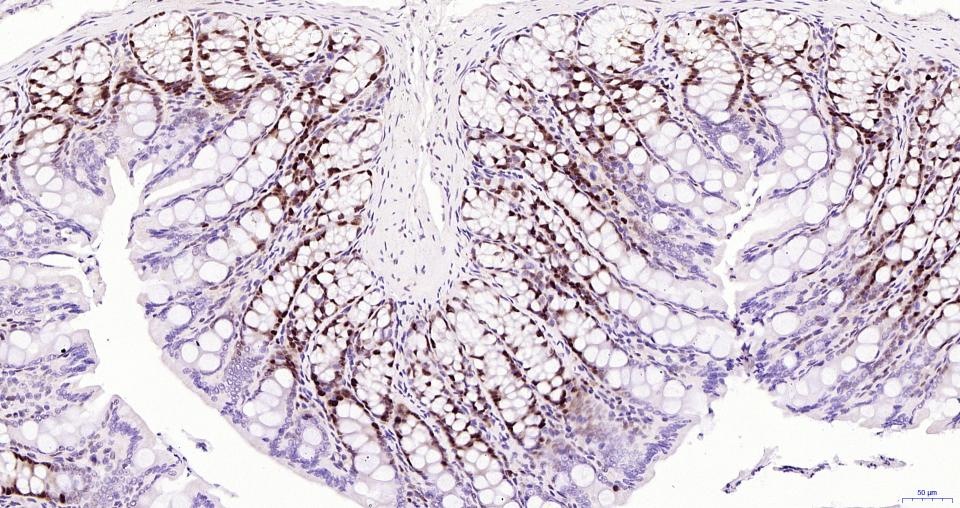

Paraformaldehyde-fixed, paraffin embedded Human Colon; Antigen retrieval by boiling in sodium citrate buffer (pH6.0) for 15 min; Antibody incubation with PCNA Polyclonal Antibody, Unconjugated (bs-0754R) at 1:800 overnight at 4°C, followed by conjugation to the SP Kit (Rabbit, SP-0023) and DAB (C-0010) staining.